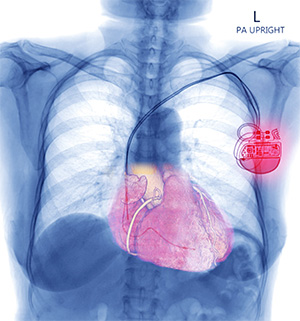

X-ray image showing a CIED